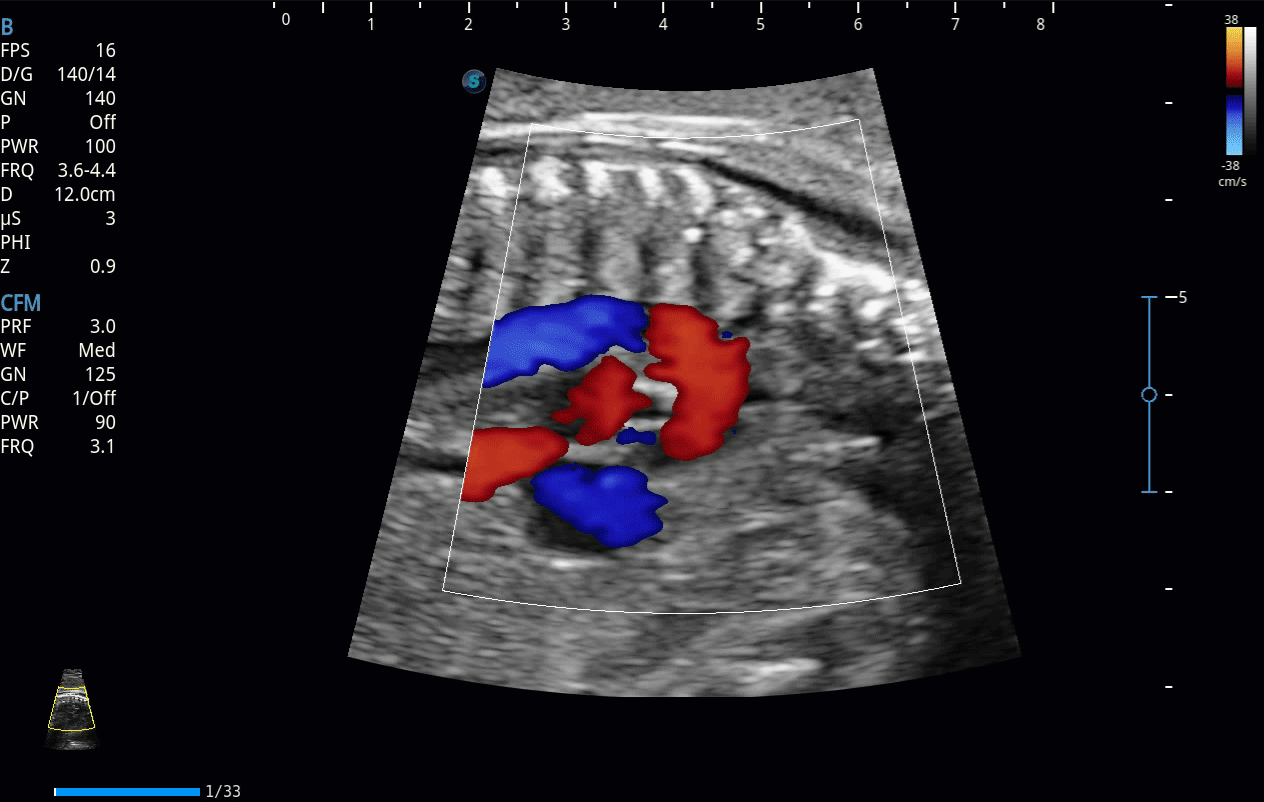

開立醫(yī)療通過不斷的技術(shù)創(chuàng)新,為大眾的生命健康提供持續(xù)關(guān)愛。P12 Plus采用全新一代超聲成像平臺(tái),新平臺(tái)旨在將真實(shí)還原組織解剖結(jié)構(gòu)作為首要目標(biāo)。平臺(tái)采用全新集成化硬件模塊,搭載新一代芯片,系統(tǒng)性能得到大幅提升,為您的診斷提供了豐富的臨床信息。優(yōu)異的圖像表現(xiàn),豐富的探頭配置,全面的應(yīng)用功能,為您日常診斷提供了可靠的助手。

彩色多普勒超聲診斷系統(tǒng)